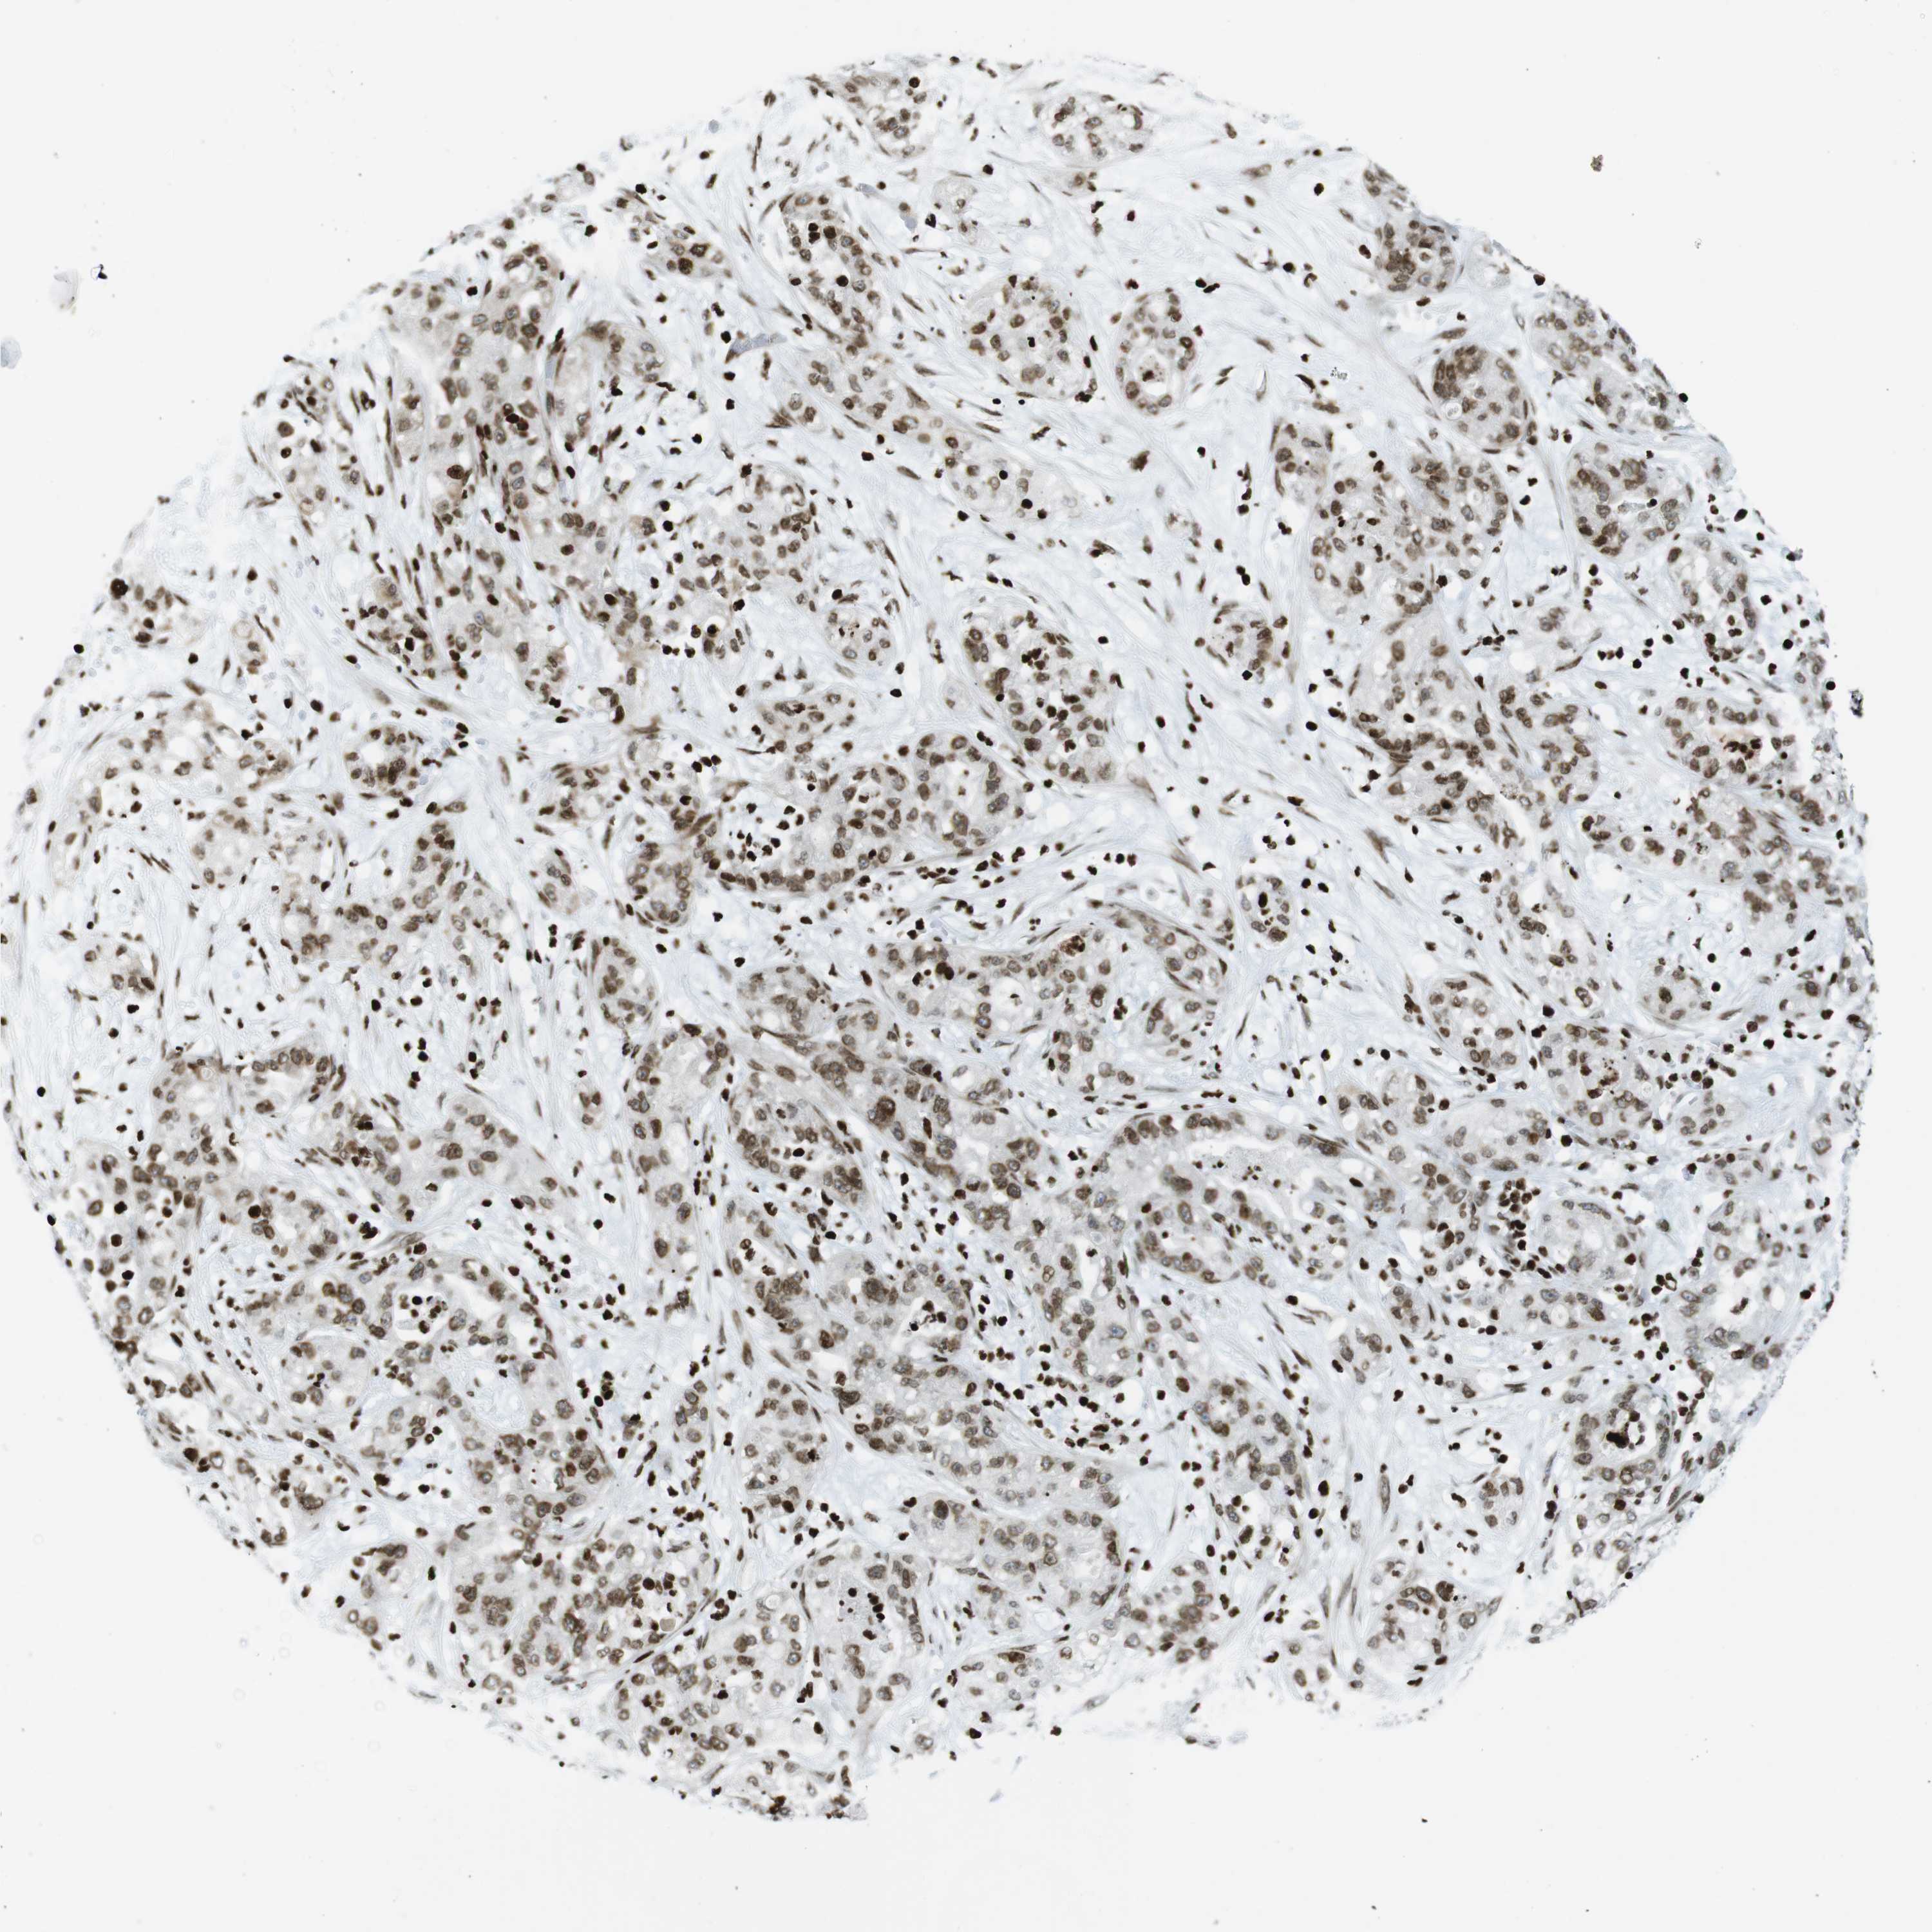

PANCREATIC CANCER - Protein expressioni

A mouse-over function shows sample information and annotation data. Click on an image to view it in a full screen mode. Samples can be filtered based on level of antibody staining by selecting one or several of the following categories: high, medium, low and not detected. The assay and annotation is described here.

Note that samples used for immunohistochemistry by the Human Protein Atlas do not correspond to samples in the TCGA dataset.

Antibody stainingi

Antibody staining in the annotated cell types in the current human tissue is reported as not detected, low, medium, or high, based on conventional immunohistochemistry profiling in selected tissues. This score is based on the combination of the staining intensity and fraction of stained cells.

Each image is clickable and will lead to virtual microscopy that enables deeper exploration of all samples and also displays staining intensity scores, fraction scores and subcellular localization as well as patient and tissue information for each sample.

Antibody HPA041189

Antibody CAB012242

Staining

High

Medium

Low

Not detected

Intensity

Strong

Moderate

Weak

Negative

Quantity

>75%

75%-25%

<25%

None

Location

Nuclear

Cytoplasmic/membranous

Cytoplasmic/membranous,nuclear

Adenocarcinoma, NOS

Adenocarcinoma, metastatic, NOS